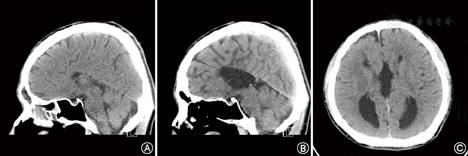

临床资料 患者男,35岁,独子,未婚,工人。以"反复情绪不稳、敏感多疑、言行异常11年"为主诉于2016年10月11日收入我院。2006年4月患者与同事争吵后出现夜眠差,情绪低落,至我院住院,诊断为"抑郁症",给予氯米帕明50~100 mg/d及米氮平15~45 mg/d,头颅MRI及增强扫描提示先天性胼胝体缺如,住院治疗42 d临床治愈出院。2008年12月患者因出现兴奋、话多、易激惹约15 d,再次住院诊断为"双相情感障碍",给予丙戊酸镁缓释片0.5~0.75 g/d、喹硫平0.5~1.2 g/d、碳酸锂0.25~1.00 g/d,住院治疗38 d临床治愈出院。2011年6月患者因失恋及同事关系紧张,出现敏感多疑,认为单位同事在背后议论自己,说自己坏话,认为同事串通起来为难自己,为此心情不好,不想上班,有打人骂人等冲动行为,再次入住我院,诊断为"精神分裂症",给予丙戊酸镁缓释片0.5 g/d、阿立哌唑口崩片10~20 mg/d,考虑患者有精神症状及情绪不稳,后换用喹硫平0.4~0.6 g/d,住院治疗33 d临床治愈出院。此后6年患者坚持服药,但因人际关系紧张(总觉得同事针对自己)而不想上班,每年均非自愿被家属送医院住院治疗,每次住院时间34~67 d,均诊断为"精神分裂症",给予喹硫平0.2~1.2 g/d、利培酮2~6 mg/d、丙戊酸镁缓释片0.5 g/d等药物治疗,每次临床治愈出院。近10年住院8次,每次均在我院住院治疗。2015年3月住院期间头颅CT结果示胼胝体正常结构未显示,第三脑室及侧脑室后角明显扩大,双侧侧脑室体部分离(见图1)。2016年10月末次住院期间,神经系统检查未见异常。实验室检查:血常规、甲状腺功能、生化全套、传染病检查及心电图、胸部CT检查均未见异常,同型半胱氨酸31.88 μmol/L(正常值4.0~15.4 μmol/L)。2017年8月电话随访:患者正常上班,坚持服用喹硫平0.4 g/d,患者或其母亲定期到门诊取药,社会功能正常,4个月前取得驾照。患者能坚持服药,但自知力不全,主动复诊较少,大部分时间其父母至门诊复诊取药。

A和B为矢状位,C为轴位

胼胝体缺如患者诊断并不困难,依据头颅CT或者MRI即可明确,胼胝体缺如的影像学特征性表现为侧脑室分离,第三脑室扩大上移[9]。但治疗只能予以对症处理,针对患者情绪症状及精神症状给予抗抑郁药及小剂量抗精神病药治疗,同时加强心理治疗,并定期随访观察。